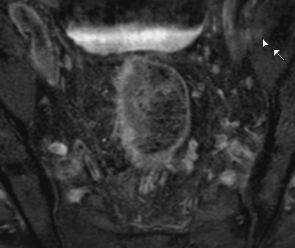

| MRT: T2-Tumor | 61-jähriger Mann mit G2-Adenokarzinom des Rektums von 8-14 cm. T2-Tumor ohne Hinweis auf Wandüberschreitung.![]() |

![]() |